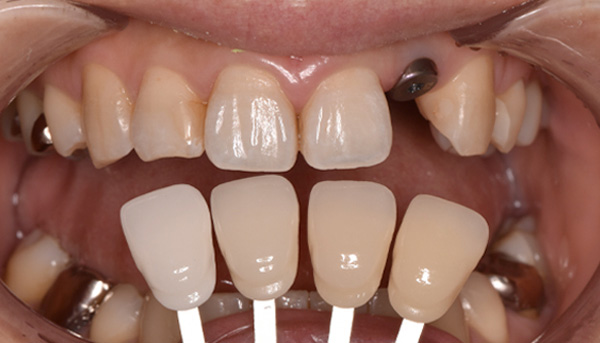

【50代女性】前歯のインプラント症例

「前歯は第一印象に関わるので失敗したくない」

治療中

治療後

津田先生からのコメント

前歯のインプラントで特に審美的に要求の高い患者様でしたので、当院で最も信頼性の高いインプラント治療プランをご選択いただきました。

| 主訴 | 抜けたままで放置していた前歯をインプラントにして綺麗にしたい。 |

|---|---|

| 治療期間 | 約4ヶ月 |

| 治療費 | 1本あたり550,000円(税別) |

| 治療内容 | 前歯のインプラント治療 |

| 治療のリスク | 前歯のインプラント治療では、審美性の問題や骨密度不足によるインプラントの不安定、神経損傷や感染のリスクがあり、術後の腫れや痛みも発生する可能性があります。 |